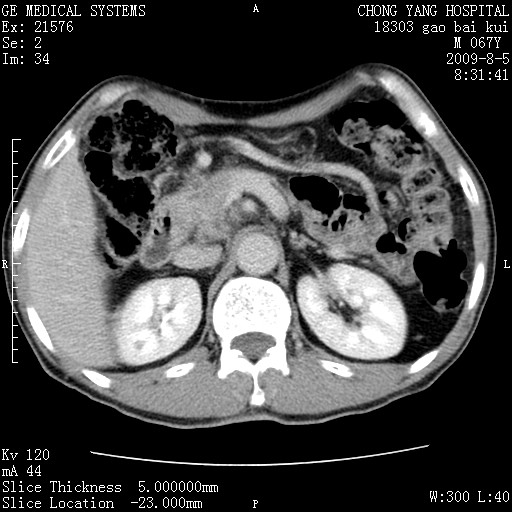

这个也过了,考虑胰腺钩突癌或壶腹癌,不除外胰管粘液乳头瘤伴胰管扩张,肝内胆管积气.

1)考虑胰头癌或壶腹癌并胰管扩张。2)肝外胆管扩张、积气,胆囊影未见;考虑术后改变。3)胃壁增厚?建议必要时行胃镜检查。

考虑胰头癌并十二指肠受侵。